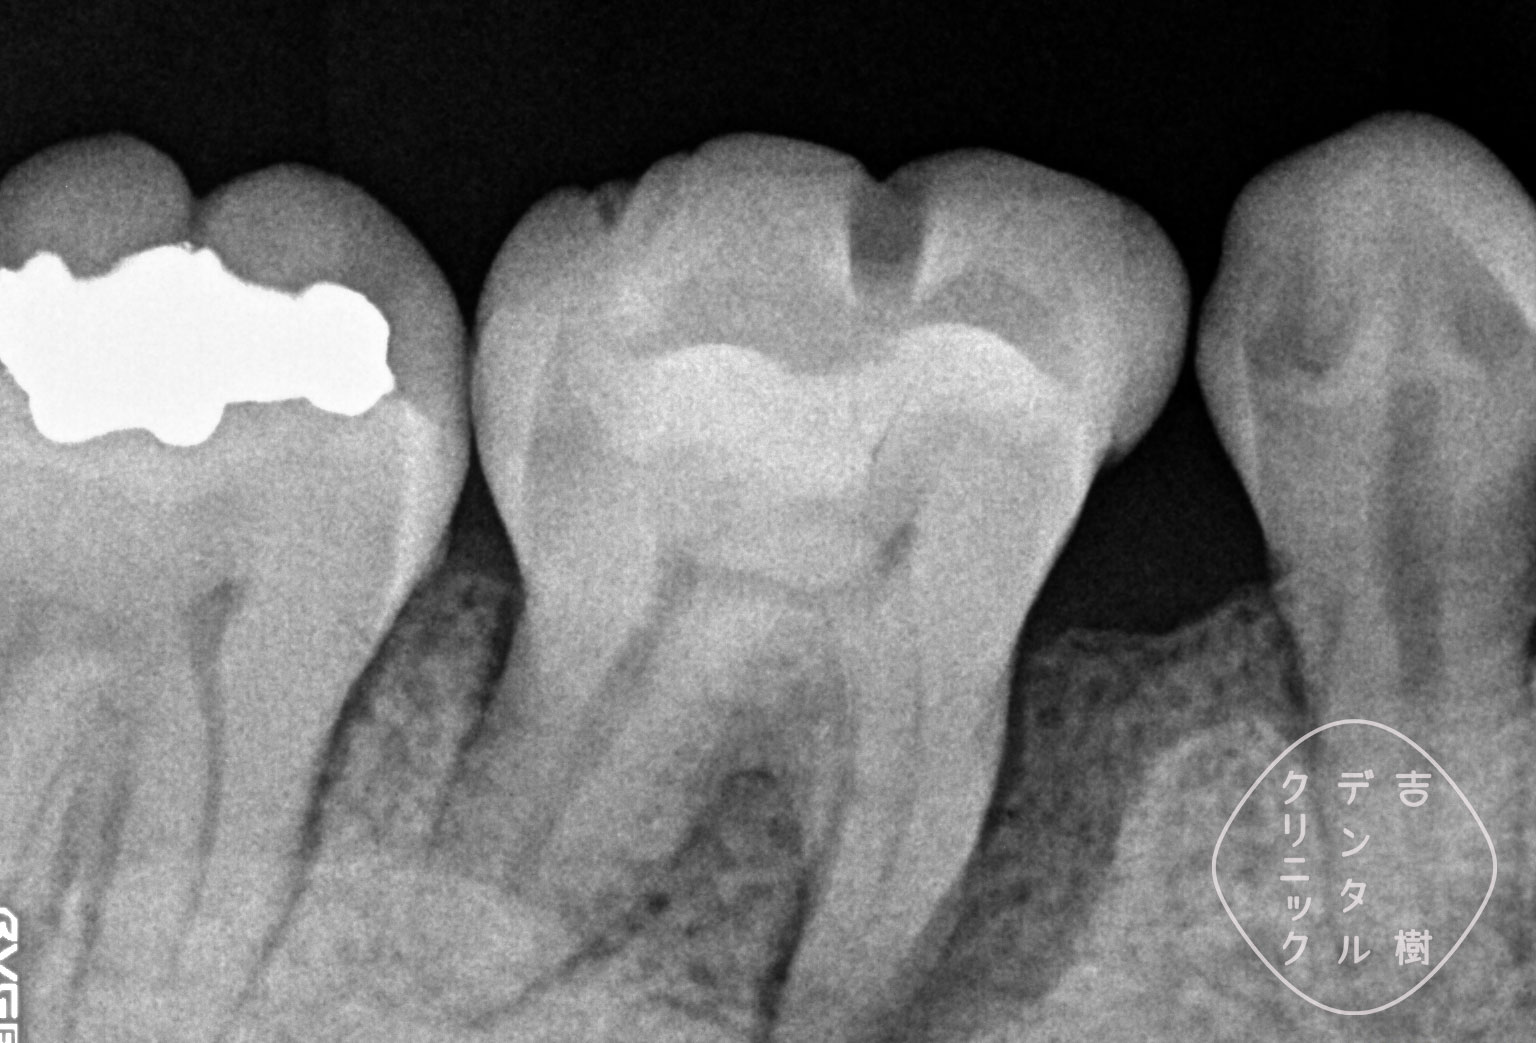

「歯周組織再生療法」により、失われた骨を再生した症例。

重度の歯周病で溶けてしまった骨を、「歯周組織再生療法」で再生した症例。